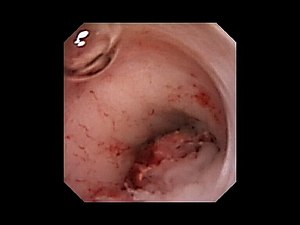

A cystoscope showing a tumor in the ureters. Here it threatens to completely cut off flow to the ureters.